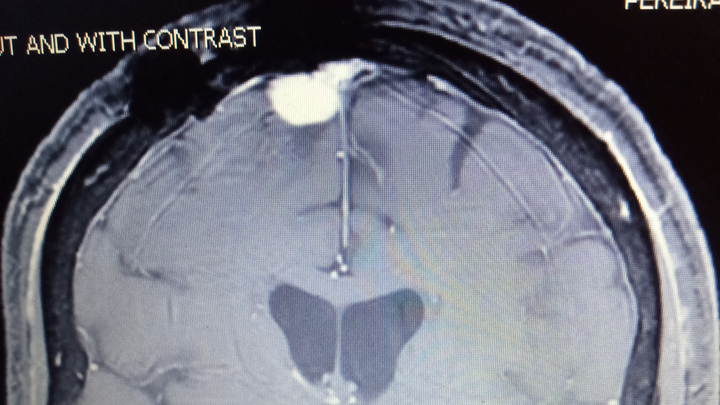

Unfortunately, my brain tumor is growing and with a second craniotomy, location of the tumor, I am likely to encounter more difficulties (possible stroke, more vision loss, more seizures, and more intense falls). I will also need radiation to the remaining tumor to hopefully stunt the possibility of regrowth.